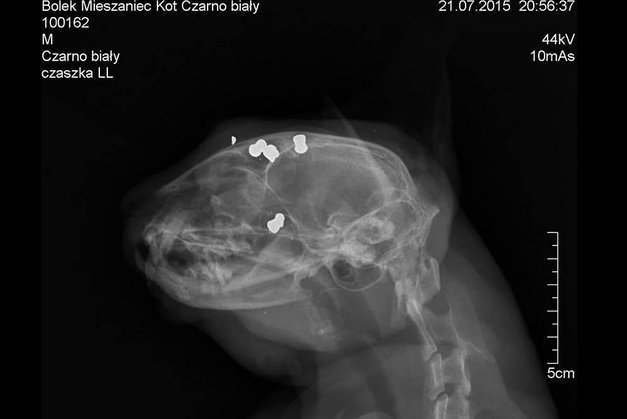

Skatowane zwierzę zostało znalezione przez mieszkańców Nysy w woj. opolskim. Kot z trudem się poruszał, ale wciąż był żywy. Po wstępnych badaniach weterynarz stwierdził, że ma rany postrzałowe z broni sportowej. Zdjęcia rentgenowskie pokazały cztery śruciny w głowie i cztery w tylnej części ciała. Oprawca traktował zwierzę jako tarczę strzelniczą. Teraz jest poszukiwany przez policję.

Znaleziony kot był w strasznym stanie, ze śladami wiązania na szyi i łapkach. – Zakrwawiony, miał obdartą z sierści szyję i rozległe rany – opowiada Magdalena Kucfir z Nyskiego Pogotowia Opiekuńczo-Adopcyjnego dla Zwierząt "Łapa". Weterynarze szybko musieli wyjąć śruciny z jego ciała. Operacja trwała prawie trzy godziny, ale na szczęście udało się uratować życie kociaka.

Obecnie czuje się dobrze. Wkrótce czeka go jednak kolejny zabieg, w którym specjaliści będą starali się przywrócić kotu wzrok. Będący przyczyną ślepoty krwiak powoli ustępuje, więc lekarze są dobrej myśli. Zwierzę dostało imię Bolek i przebywa u ludzi, którzy go przygarnęli.